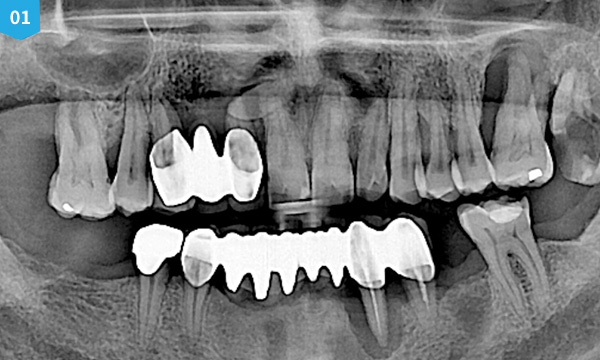

현재 치아의 상태를 정확하게 검진하는 것이 매우 중요합니다. 치아가 소실 된 시간이 오래될 수록 잇몸 뼈의 소실량이 많아지기 때문에 임플란트를 식립할 수 있는 잇몸뼈의 양과 질을 철저하게 분석하는 것이 매우 중요합니다.

고정성 전악 임플란트의 경우 식립할 임플란트의 갯수, 일정 등 나의 구강 상태를 고려한 진료 계획을 수립하여 계획에 맞게 임플란트를 식립합니다.

치료 케이스 보기

before

after